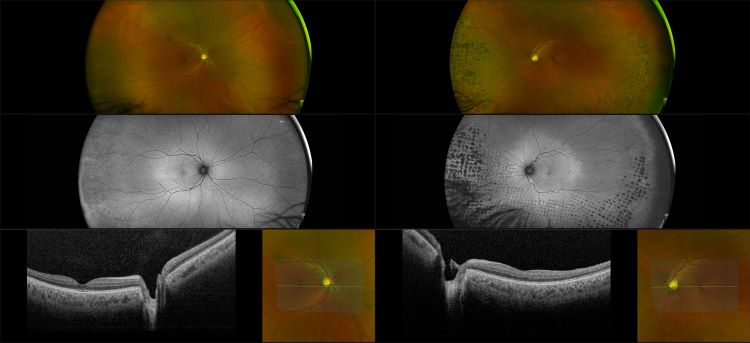

Silverstone - BRVO with Nevus - Full steer - RG, AF, OCT

Branch retinal vein occlusion can be caused by thrombosis but is more likely to be produced by compression due to arteriolosclerosis. This occurs at arteriovenous crossing sites where there is a common adventitial sheath of each vessel. Marked A/V nicking usually precedes the occlusive process.